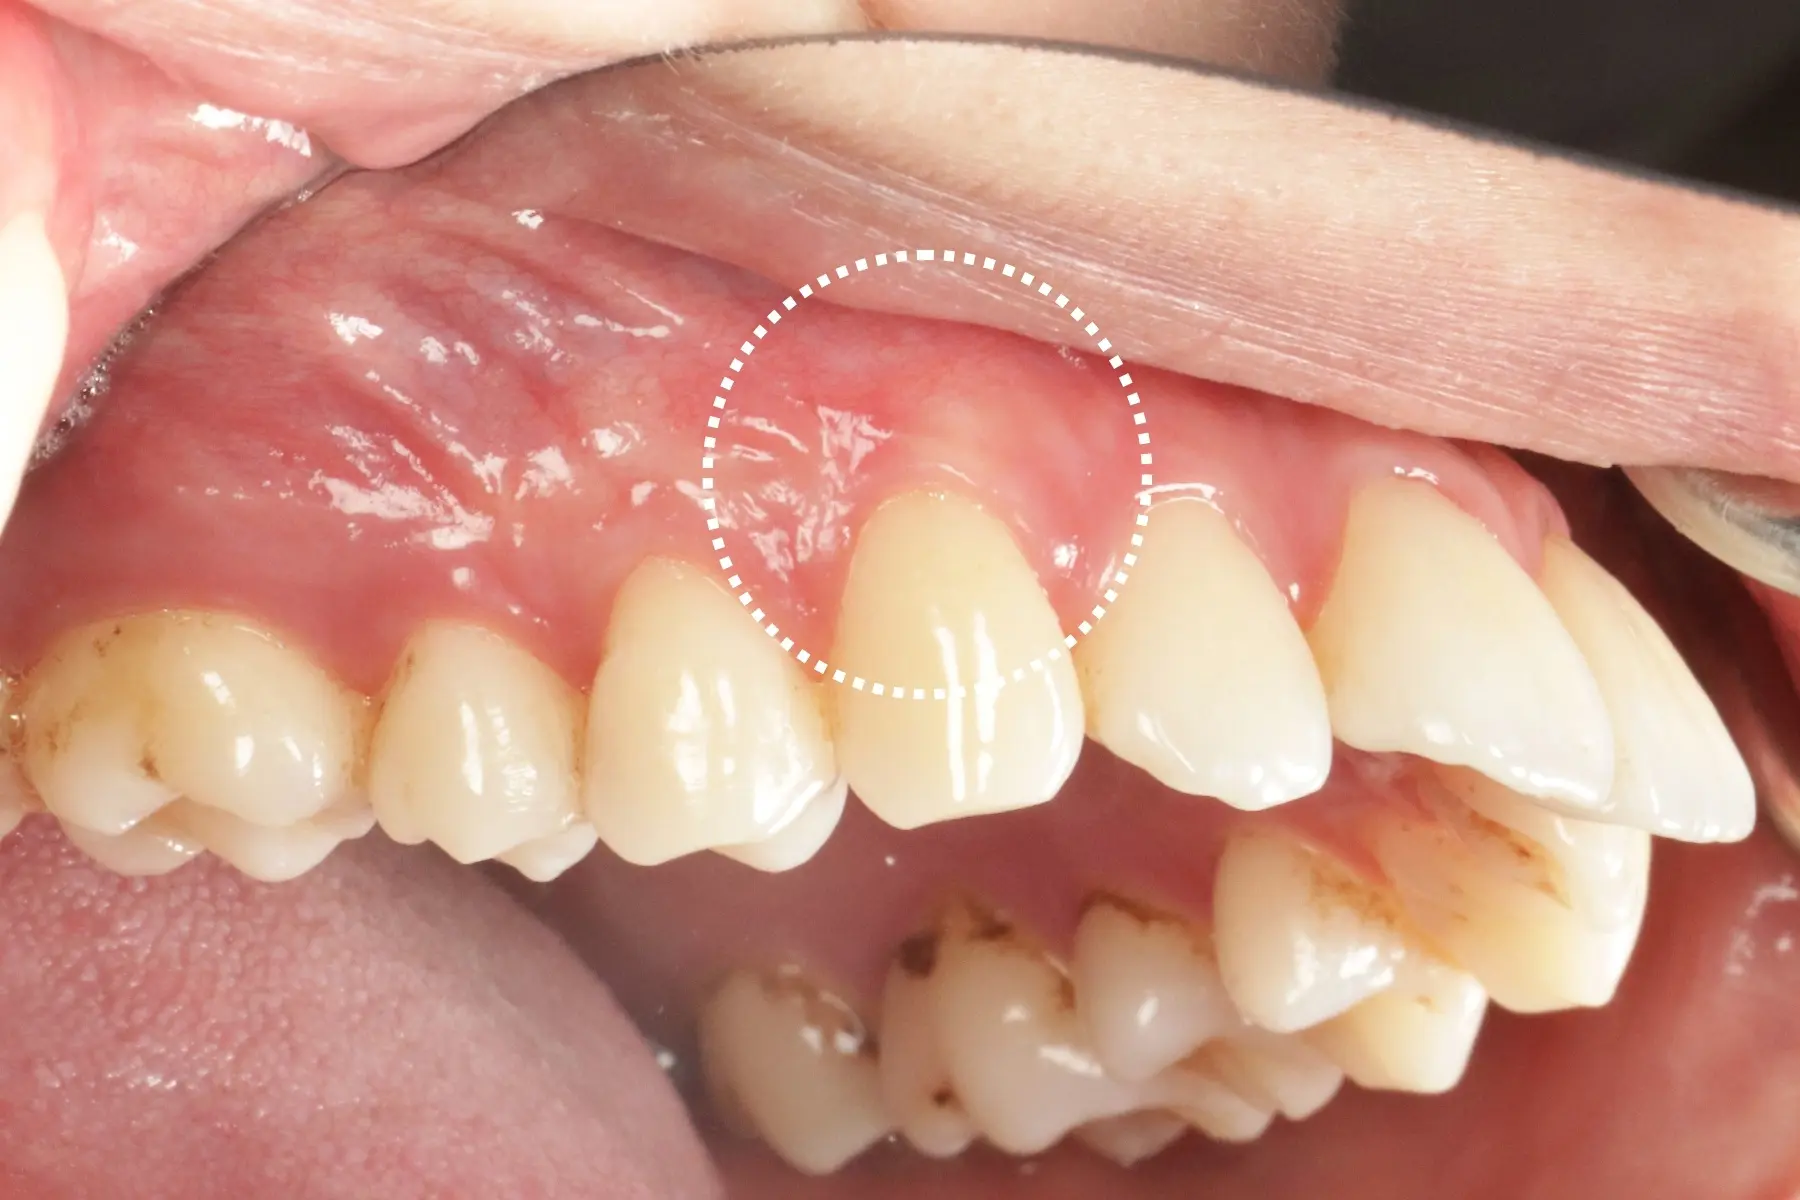

• 術前 42

術後 40

牙周治療

主治醫師

• 鍾國耀

治療時間

三次療程

主訴

右上前牙牙齦反覆腫脹化膿